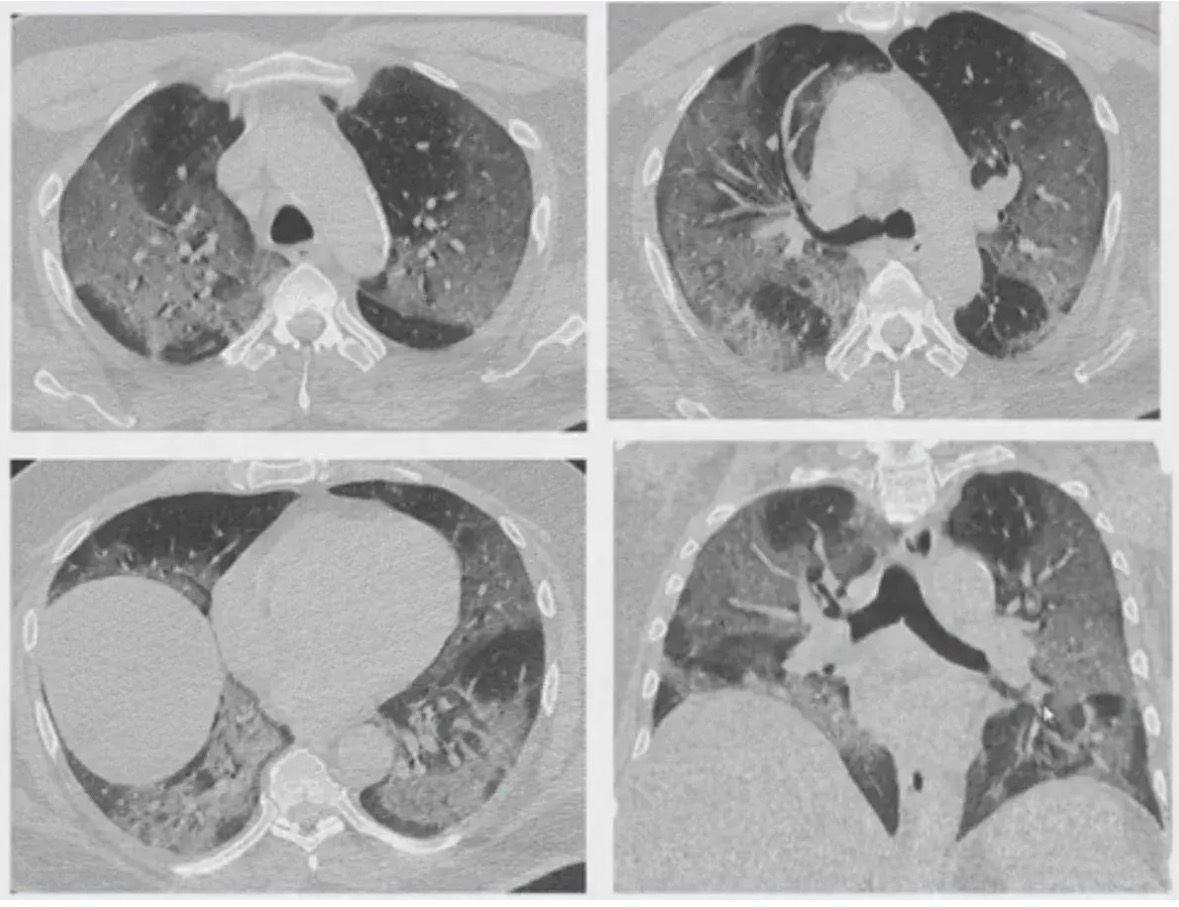

Зимой наряду с подъёмом заболеваемости ОРВИ и гриппом, отмечается рост заболеваемости вирусными пневмониями

Вирусная пневмония – острое воспаление респираторных отделов легких, вызываемые вирусами, протекающие с синдромом интоксикации и дыхательных расстройств. " Частые причины вирусных пневмоний:

Для вирусной пневмонии характерно острое начало заболевания с высокой температурой, симптомами интоксикации, катаральными явлениями (першение в горле, заложенность носа) , сухим кашлем. При развитии дыхательной недостаточности появляется чувство нехватки воздуха, одышка. Нередко к вирусной пневмонии присоединяется бактериальная инфекция, пневмония становится вирусно-бактериальной, что утяжеляет ее течение.